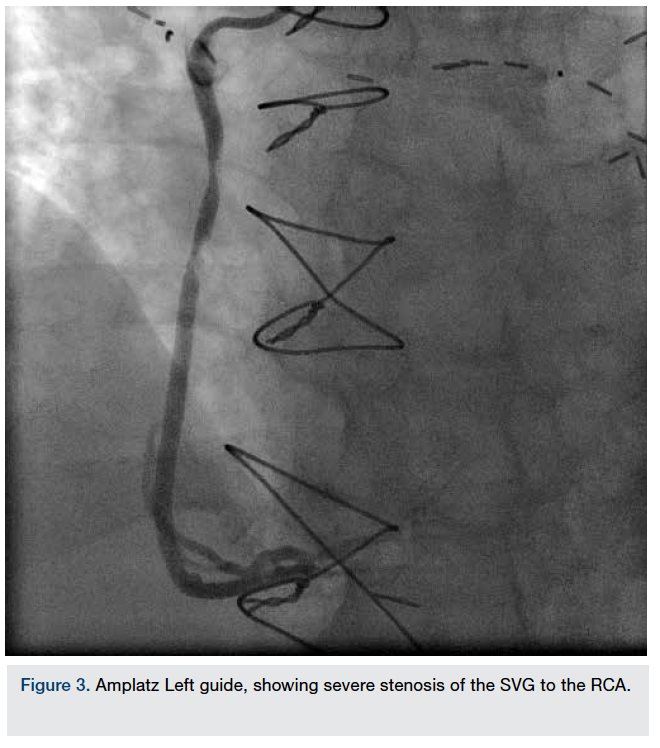

The coronary angiogram showed a 100% occluded proximal RCA and a long area of heavily calcified 90% stenosis in the mid LAD. The left main and left circumflex arteries were patent with mild disease. The SVG to the LAD was widely patent with mild degenerative changes and an excellent run-off to the LAD. The SVG to the RCA had severe proximal and body of the graft stenosis (Figure 3).

A 6 French Amplatz Left (AL) 2 guide was used to cannulate the SVG to the RCA. Additional heparin was used for weight-based anticoagulation. After deploying a 5 mm Spider filter (ev3) in the SVG to the RCA, a 4.0 x 26 mm Integrity bare-metal stent (Medtronic) was deployed by direct stenting, with a good final angiographic result (Figure 4).